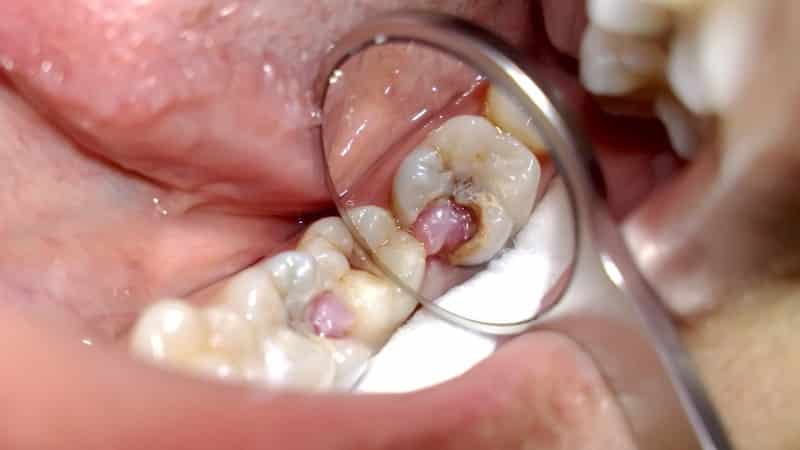

Хронический гипертрофический пульпит является довольно редким вариантом, чаще всего встречающимся у молодых людей. В этом случае поражается коронка зуба. Симптомы могут проявляться не всегда, а боли обычно слабо выражены, без реакции на раздражители.

При осмотре можно заметить гипертрофию или полип в полости зуба. В некоторых случаях новообразование мешает человеку полностью закрыть челюсти и нормально пережевывать пищу. Часто наблюдается кровоточивость нароста.

Гипертрофическая форма отличается незначительной клинической картиной. Основным симптомом является, пожалуй, тупая боль. В редких случаях может наблюдаться кровоточивость во время еды, что связано с разрастанием пульпы и ее механическим повреждением. Этот признак вызывает беспокойство у пациента и часто становится причиной обращения к врачу.